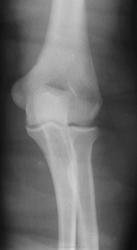

Молодой мужчина. Постоянный дискомфорт и боли в локте.

Так-то вроде бы ничего криминального. Два поперечных артефакта не в счет. Смущает продольная линейная тень, похожая на склероз борозды локтевого нерва (раньше такого не видел). Вообще, если товарищ занимается физическим трудом или физкультурой, после прекращения нагрузок боли обычно стихают.

сужение суставной щели в боковой проекции плечелоктевого сустава, в прямой зияние плечелучевой щели, в прямой деформация продольной оси и видимое переразгибание. Диагноз: потеря стабилизации связочного аппарата.

Нечеткость наружного контура мыщелков плечевой кости... Вроде бы и всё. Наверное погрешность съемки?

мне проксимальный метафиз локтевой кости смотрится несколько подвздутым, больше изменений не увидел, взаимоотношение костей в лотевом суставе правильное.